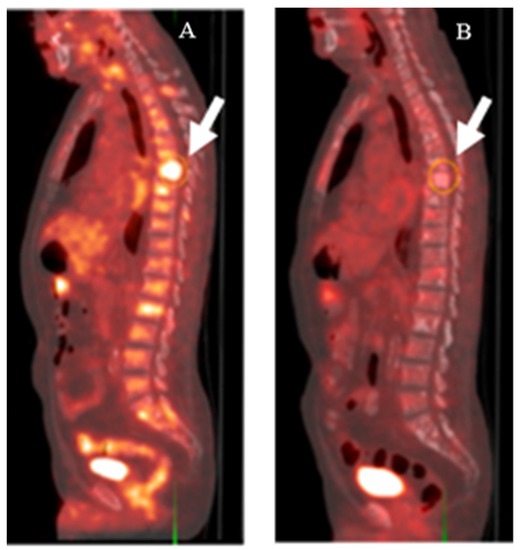

Figure 2. [18F]FDG-PET imaging of a patient with CRPC before (A) and after (B) treatment with docetaxel. Metabolic activity in thoracic spine lesions (white arrows) decreased after treatment. This research was originally published in the Journal of Nuclear Medicine (JNM) [17].

Despite the limited use of [18F]FDG in the diagnosis of PCa, some studies have been performed to investigate the potential use of [18F]FDG as an auxiliary indicator in the field of PCa. The more recent investigations of [18F]FDG as an imaging agent for PCa focused on its use as a prognostic agent. Jadvar et al. stated that in patients with castration-resistant PCa, the sum of their maximum standardized uptake values (SUVmax) for all detectable lesions (a parameter derived after subtracting an SUV baseline value for normal hepatic tissue) negatively correlated with their OS [18]. Similarly, it was also shown that the time to hormone therapy failure (THTF) significantly decreased with increases in these summed SUVmax values for metabolically active lesions [19]. The role of [18F]FDG imaging in the treatment management of PCa has also been studied. Hillner et al. reported that in 35% of PCa patients, after imaging, their management was changed from treatment to nontreatment, or vice versa. However, that was still lower than for other cancers, such as small cell lung cancer and myeloma [20]. Recently, it was reported that despite only moderate detection rates of 16.7% for [18F]FDG PET/CT scans used on PCa patients with negative [68Ga]Ga-PSMA-11 PET/CT scans, the patients with positive [18F]FDG scans possessed higher PSA levels and GSCs compared to patients with negative scans [21]. These data suggest that [18F]FDG-imaging of PCa could be used as an auxiliary diagnostic tool in patients with high PSA values and GSCs, but who had produced negative PSMA-based PET/CT results.